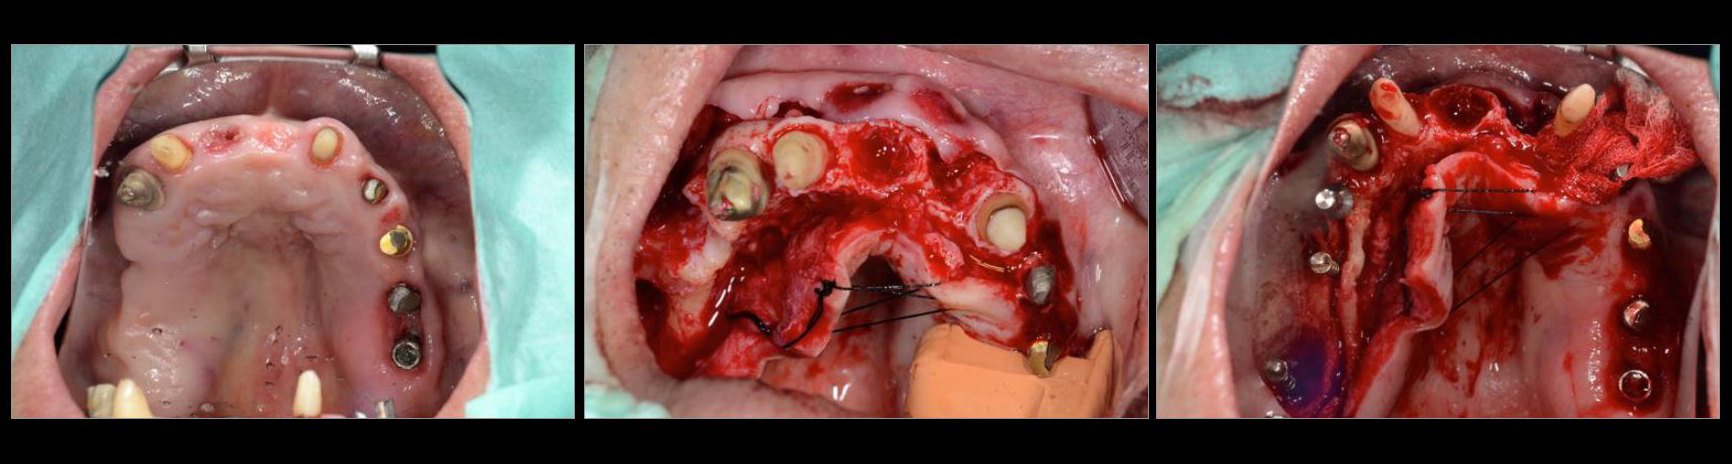

治療中01

治療中02

治療中03

治療中04